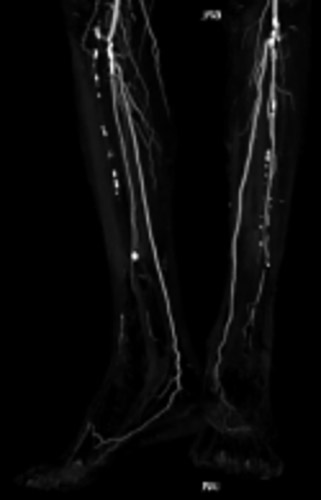

同側順行アプローチにて造影を行うと前回治療したPA(Peroneal Artery)は開存しており、ATA(Anterior Tibial Artery)は入口部から閉塞していた(図1)。末梢部分のDA(Dorsal Artery)は確認出来た(図2)。

DAは閉塞していたが内腔はあるので穿刺を検討したが、難しいと判断しPTAを穿刺した。PTA経由でATAにレトログレードアプローチを行いDAからシースを挿入するため、1gワイヤーを進めたがATA(Anterior Tibial Artery)方向へワイヤリング出来ないため、Zizai™をPOP方向へ進め造影した(図3)。ATA入口部は狭窄しており、更に末梢は閉塞していることを確認した。ATA入口部へワイヤー通過に成功し急峻な角度ではあったがZizai™を追従させ(図4)、ATAは閉塞血管でありワイヤールートはSubでも良いと判断しワイヤーナックルにて末梢まで進めた。DAを18G針で穿刺をしワイヤーランデブーに成功した(図5)。その後、DAに4Frシースを挿入し、2.5㎜径バルーンでATAを拡張したあと、PTAのワイヤーとZizai™を抜去後にアプローチサイトの止血を行い、ATAの4Frシースからガイディングシースへ入れ替えを行った。